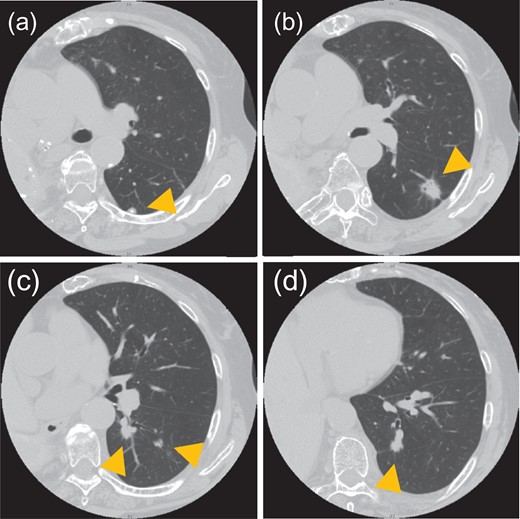

An asymptomatic 82-year-old woman with no smoking history presented with a history of two surgeries of the right lung. She had undergone surgery for lung adenocarcinoma of the right upper lobe at another institution in 1990 and for residual right lung adenocarcinoma at our institution in 1996. Follow-up had been performed at another hospital since 2008. In September 2013, nodules were discovered in the patient’s left lower lobe on follow-up computed tomography (CT); she returned to our institution for further care. The nodules in the left lung had grown, and several new nodules had appeared. CT showed five nodules in the lower lobe of the left lung, all of which were located in segments 6 and 10a (Fig. 1). The size of the largest nodule was 2.1 cm. These nodules were suspected to be synchronous multiple lung cancer, because each had a ground-glass appearance. On respiratory function tests, the patient had a vital capacity (VC) of 840 ml, %VC of 45.7%, forced expiratory volume in 1 s (FEV1.0) of 610 ml and %FEV1.0 of 72.6%. However, the patient was able to climb stairs and did not have shortness of breath. In the assessment of the cardiac function, electrocardiogram showed regular sinus rhythm, and no ischemic changes. Echocardiogram showed an ejection fraction of 84%, no right heart strain and good wall motion.

CT shows five nodules in the left lower lobe. Tumor sizes and locations: (a) 0.8 cm in S6a, (b) 2.1 cm in S6a, (c) 1.3 cm and 0.8 cm in S6c and (d) 1.1 cm in S10a. All nodules were located in S6 or S10a.